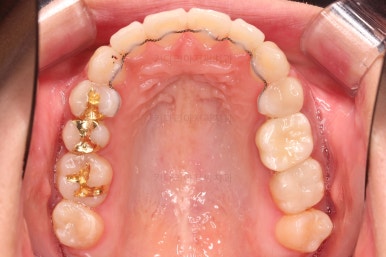

마찬가지로 초진 시 입안의 모습입니다.

입안 사진을 보니 문제점이 보이죠.

바로 어금니가 없는 상태였습니다.

틈이 다 없어졌고, 교합도 양호합니다.

무엇보다 임플란트 없이 결손부위가 깔끔하게 채워졌고요.

매우 다행으로 사랑니도 다 있었기 때문에 마치 큰 어금니가 다 있는 것과 같은 상황이 되었습니다.

입안의 모습은 더할나위 없이 잘 개선되었고요.

상하좌우 이 뽑은 위치와 크기가 달라 이정도 중앙선은 매우 잘 맞는 상황인거고요.